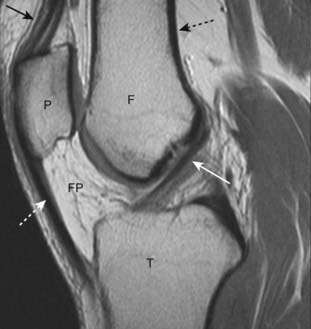

image

Figure 21-2 Normal MRI of knee.

A sagittal view of the knee demonstrates the superior display of the internal matrix of bone and the surrounding soft tissues. There is fatty marrow in the distal femur (F), proximal tibia (T), and patella (P). The quadriceps (solid black arrow) and patellar (dotted white arrow) tendons are shown. The anterior cruciate ligament (solid white arrow) is visible. There is bright signal fat in the infrapatellar fat pad (FP). Notice how the cortex of bone has a very weak signal (dotted black arrow).